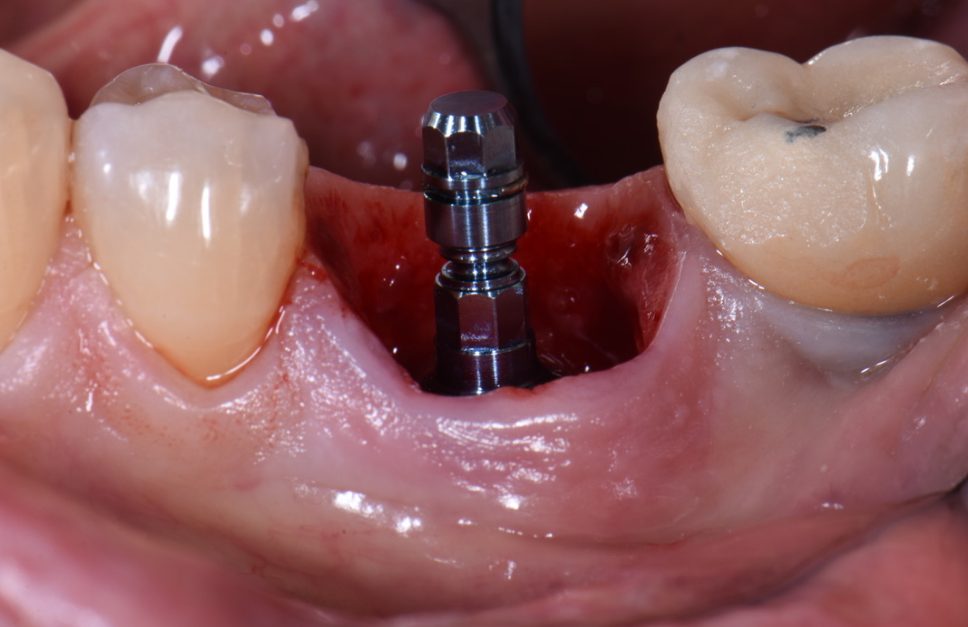

ایمپلنتها با قرارگیری در بافت لثه و زیر استخوان فک، نقش ریشه دندان طبیعی را ایفا میکنند. در واقع، ایمپلنت دندان یک پیچ فلزی است که به داخل استخوان قرار میگیرد و پس از گذشت مدتزمانی، با بافت آن ادغام میشود. این پیچ به گونهای طراحی شده که به عنوان یک جسم خارجی شناخته نشود و هماهنگی مناسبی با فک شما خواهد داشت.

ایمپلنتها به عنوان جایگزینی برای دندانهای از دست رفته طراحی شدهاند. جراح با استفاده از ابزارهای مخصوص، ایمپلنت را در بافت استخوانی فک قرار میدهد تا به عنوان پایهای برای دندان مصنوعی معروف به تاج عمل کند. سپس، اباتمنت به ایمپلنت متصل میشود تا دندان مصنوعی را در جای خود نگه دارد. تاج به طور اختصاصی برای هر فرد طراحی میشود تا با شکل و رنگ دندانهای طبیعی او هماهنگ باشد. پایه ایمپلنت معمولاً از تیتانیوم ساخته میشود که به خوبی با بافت استخوان فک سازگاری دارد.

سوراخ کردن استخوان

اگر نیازی به تقویت استخوان نباشد، پس از کشیدن دندان، مرحله بعدی ایجاد سوراخ در استخوان خواهد بود. با استفاده از دریل دندانپزشکی، استخوان به اندازه مشخصی حفر میشود و ایمپلنت درون آن قرار میگیرد. سپس با استفاده از قطعهای به نام پیچ درپوش، سوراخ ایمپلنت مسدود میشود.

نصب ایمپلنت و بخیه زدن لثه

مرحله بعدی بخیه زدن لثه اطراف ایمپلنت است. دندانپزشک ممکن است لثه را به گونهای بخیه کند که قسمت بالایی ایمپلنت بیرون بماند، یا اینکه لثه را روی ایمپلنت بپوشاند و بخیه بزند تا از آن محافظت بیشتری به عمل آورد. در صورت انتخاب گزینه دوم، برای نصب روکش دندان، نیاز به یک عمل جراحی ساده وجود دارد تا لثه برش خورده و ایمپلنت نمایان شود.

نصب اباتمنت

پس از اینکه استخوان و ایمپلنت به هم متصل شدند، مرحله بعدی آغاز میشود. دندانپزشک درپوش ایمپلنت را باز کرده و قطعهای به نام اباتمنت را بر روی آن قرار میدهد. اباتمنت نقش دندان تراشیدهای را ایفا میکند که قرار است روکش بر روی آن نصب گردد و به عنوان پایهای برای اتصال روکش عمل میکند.